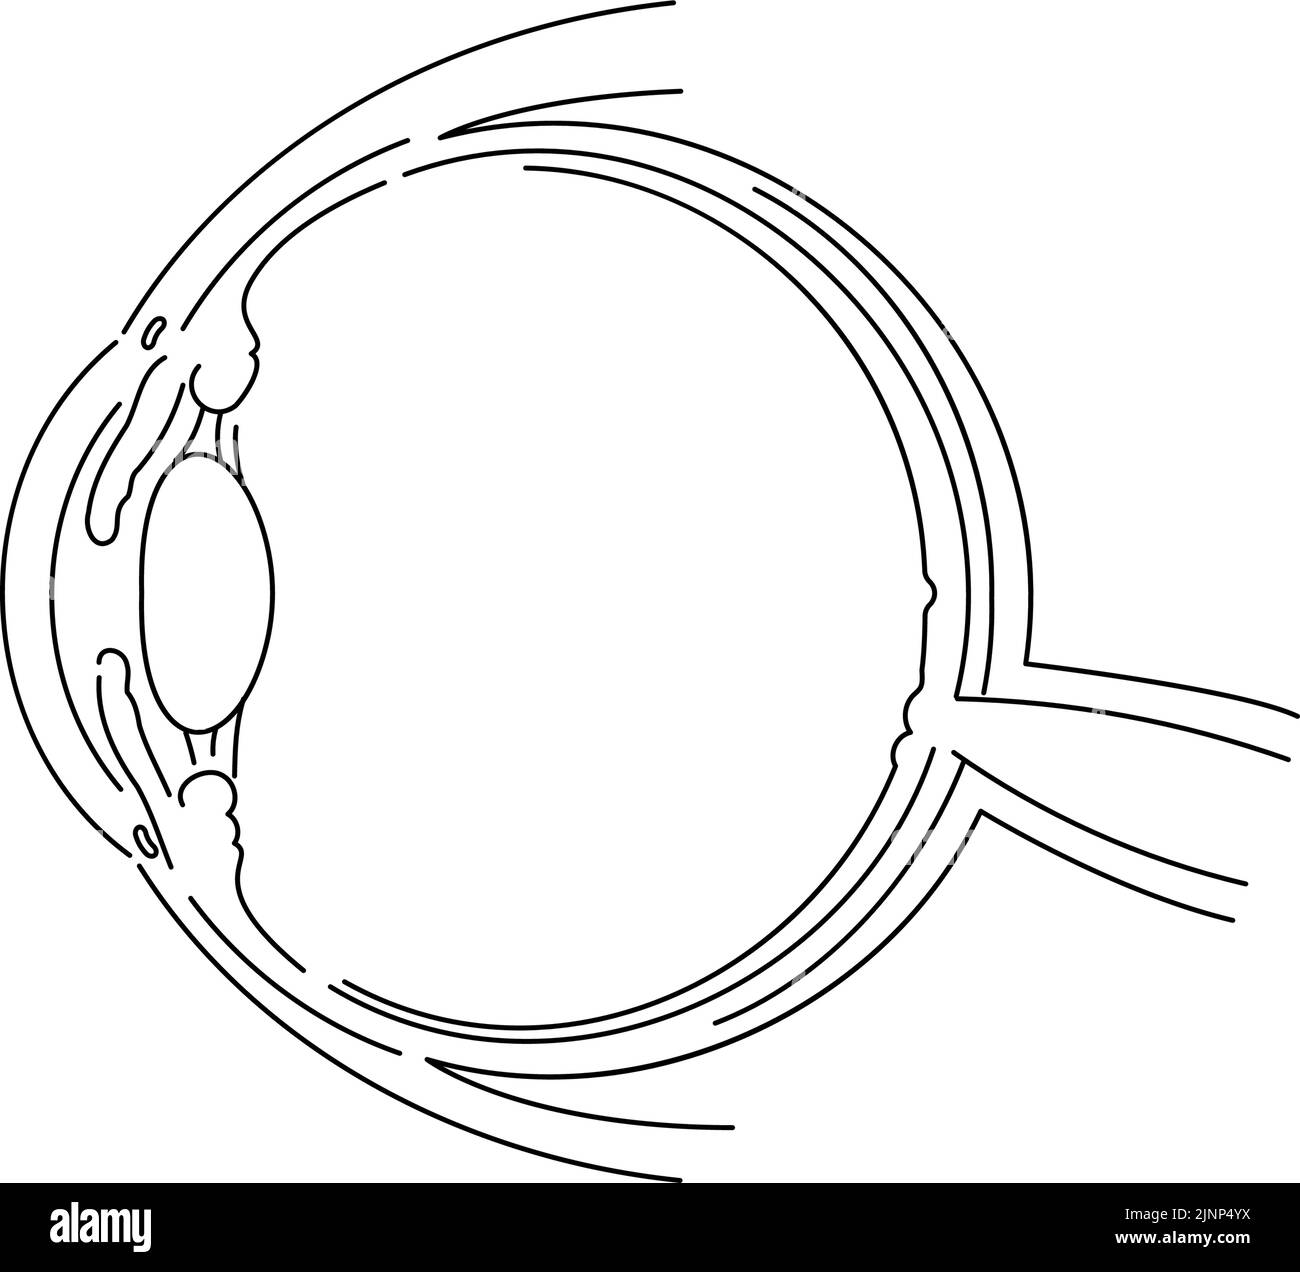

Diagrammatic illustration of the eye (line drawing) Stock Vectorhttps://www.alamy.com/image-license-details/?v=1https://www.alamy.com/diagrammatic-illustration-of-the-eye-line-drawing-image478074574.html

Diagrammatic illustration of the eye (line drawing) Stock Vectorhttps://www.alamy.com/image-license-details/?v=1https://www.alamy.com/diagrammatic-illustration-of-the-eye-line-drawing-image478074574.htmlRF2JNP4YX–Diagrammatic illustration of the eye (line drawing)

Illustration of the eye - Translation: Schlemm's canal, corner angle, aqueous humor, pupil, anterior chamber, cornea, iris, posterior chamber, ciliary Stock Vectorhttps://www.alamy.com/image-license-details/?v=1https://www.alamy.com/illustration-of-the-eye-translation-schlemms-canal-corner-angle-aqueous-humor-pupil-anterior-chamber-cornea-iris-posterior-chamber-ciliary-image478075540.html

Illustration of the eye - Translation: Schlemm's canal, corner angle, aqueous humor, pupil, anterior chamber, cornea, iris, posterior chamber, ciliary Stock Vectorhttps://www.alamy.com/image-license-details/?v=1https://www.alamy.com/illustration-of-the-eye-translation-schlemms-canal-corner-angle-aqueous-humor-pupil-anterior-chamber-cornea-iris-posterior-chamber-ciliary-image478075540.htmlRF2JNP66C–Illustration of the eye - Translation: Schlemm's canal, corner angle, aqueous humor, pupil, anterior chamber, cornea, iris, posterior chamber, ciliary